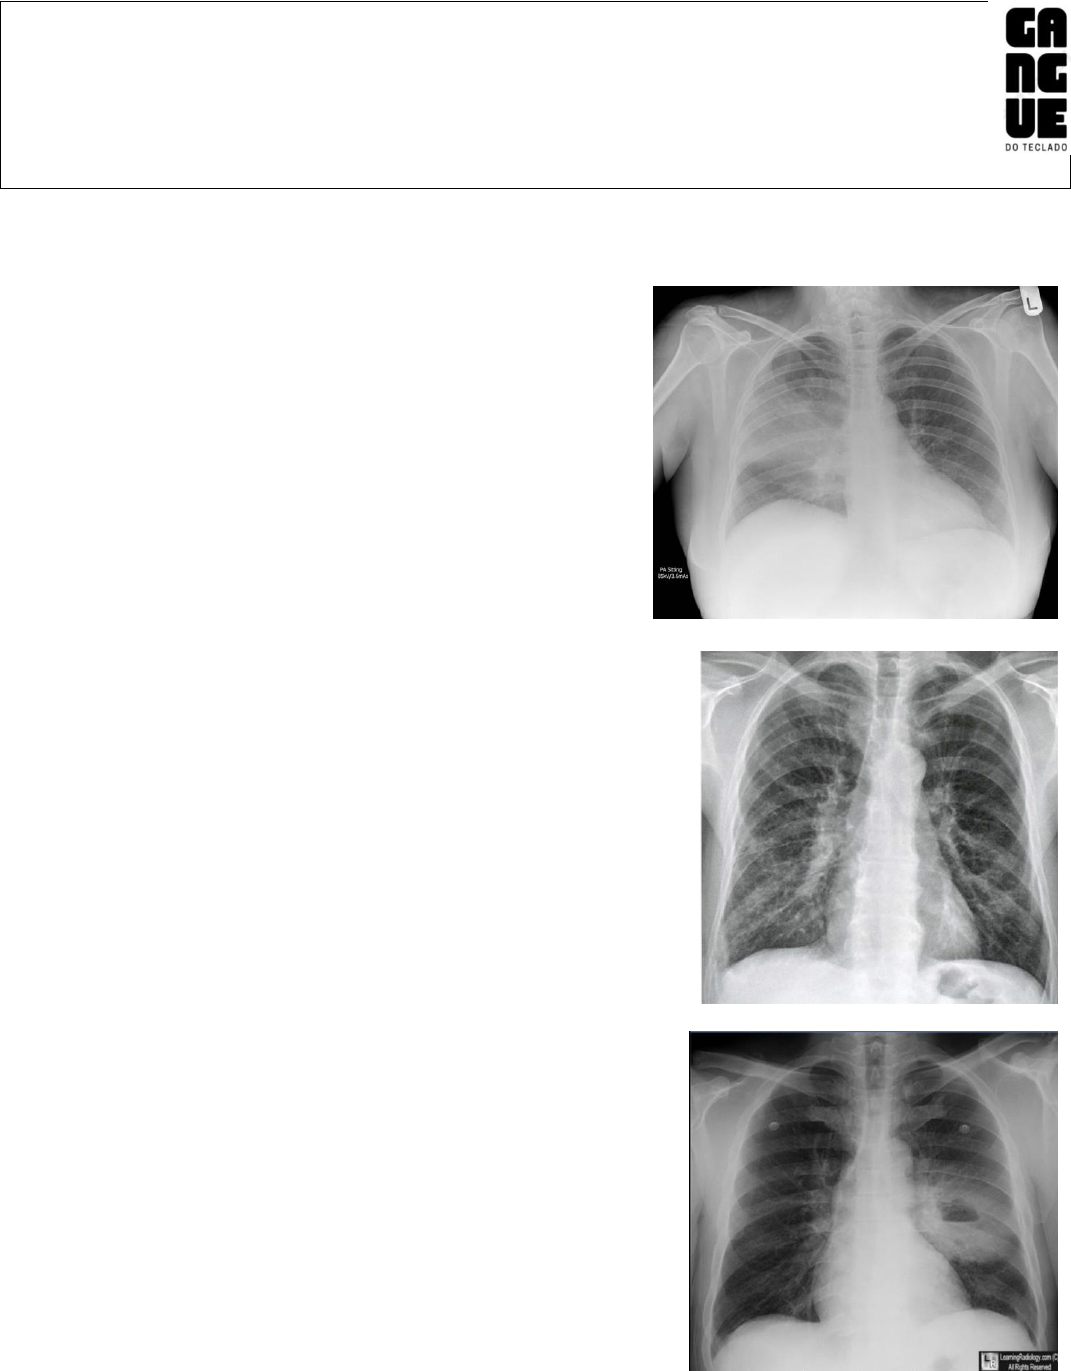

Caso 1- Sexo feminino, 40 anos

Tosse produtiva e desconforto respiratório

Na imagem: área hipotransparência em pulmão direito de

padrão alveolar

Para saber a posição exata precisaria do perfil

Diagnostico: Pneumonia lobar

Caso 2 – Sexo masculino, 27 anos

Febre baixa e dispneia há 8 dias

Na imagem: hipotransparência intersticial

Parece que tem uma redinha no 1/3 inferior

Olhar aorta mais evidente devido a idade do paciente

Geralmente causada por vírus

Diagnostico: pneumonia intersticial

Caso 3 –

Na imagem: hipotransparência ovalada de parede espessa

Ruído hidroaéreo inferior

Bolinhas na imagem são eletrodos

-Janela de parênquima (TC)

Ruído hidroaéreo no centro

Como o paciente faz deitado se houver gás ele vai tender ir para a

área anterior do corpo

Diagnostico: abscesso pulmonar